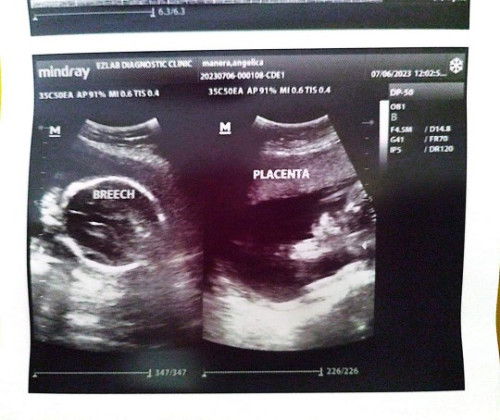

Breech baby

Hello mga mamsh, sino same case ko dito turning 24 weeks na ako tapos breech si baby. sa 1st and 2nd utz ko cephalic position sya, then knina nagpa utz kmi for the gender breech na :( medyo may konting kaba lang sa lahat ng anak ko, its my 1st time na nagkaron ng breech position. I know maagap pa para magworry but paano ginawa niyo para magbalik ceph si baby. Thanks in Advance mga mommy!